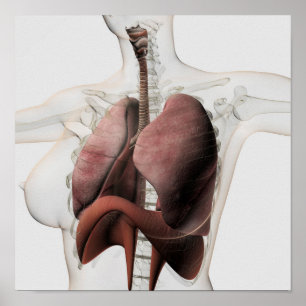

Carta do poster da anatomia do órgão interno do

Preço56,50 €